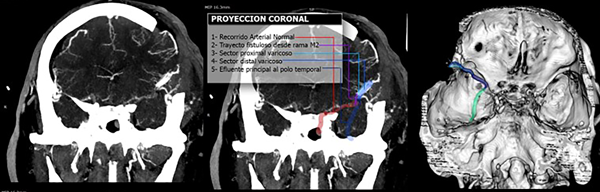

Con los datos obtenidos de este estudio se diagnostica fístula arteriovenosa cerebral, identificando su afluente principal en la cara profunda y superior del trayecto varicoso central, proviniendo aparentemente de ramas de M3 en la profundidad de la cisura silviana. El trayecto varicoso central se extiende sobre la superficie de la cisura homónima y se dirige al polo temporal sin aparente comunicación a los senos durales normales. Se grafican imágenes clave en la Figura 3.

Figura 3. Gráfica de la interpretación de la lesión vascular. En la última imagen de reconstrucción 3D se puede observar la disposición de la várice venosa central que se continúa con un tramo intradural de trayecto sui generis (verde).